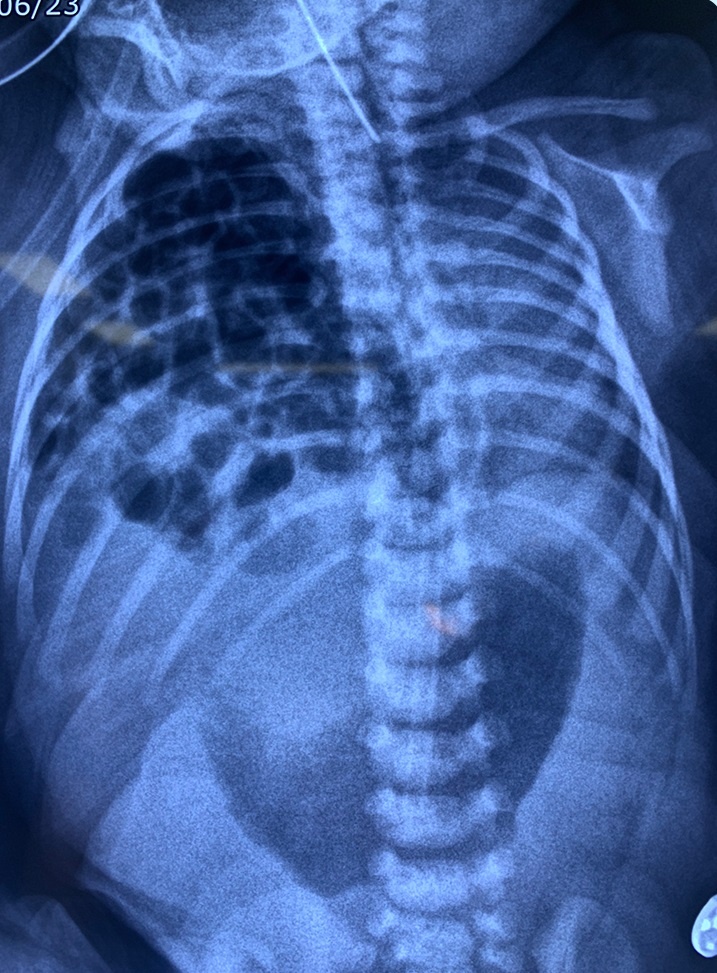

Hình ảnh siêu âm cho thấy toàn bộ ruột và một phần gan thoát ra ngoài cơ hoành của bé An.

ThS.BSNT.CKI Trần Lâm Khoa - bác sĩ chuyên phụ trách thai kỳ nguy cơ cao, Trung tâm Sản Phụ khoa BVĐK Tâm Anh - cho biết bé An được phát hiện dị tật thoát vị hoành ở tuần 21 của thai kỳ. Khi đó, một phần gan, túi mật, ruột non và ruột già bé “chui lên” lồng ngực phải, khiến phổi phải thiểu sản nghiêm trọng. Sau khi nghe bác sĩ giải thích nguy cơ bệnh lý, mẹ bé được chọc ối để tìm bất thường di truyền đi kèm, đồng thời siêu âm tim thai chuyên khoa, chụp cộng hưởng từ để tiên lượng tốt hơn cho bé. Được 38 tuần 4 ngày, thai nhi xuất hiện tràn dịch màng ngoài tim và đa ối. Bác sĩ Lâm Khoa và gia đình thống nhất cho bé sinh mổ. May mắn bé sinh đủ tháng, cân nặng 3,2 kg.

BS.CKII Nguyễn Đỗ Trọng cho biết cơ hoành là hàng rào cơ hình vòm nằm giữa khoang ngực và khoang bụng; giúp ngăn cách tim, phổi với cơ quan trong ổ bụng (dạ dày, ruột, lá lách, gan). Phần lớn trẻ bị thoát vị hoành trái (chiếm đến 80%). Trong khi đó, bé An thoát vị hoành phải. Đây là dị tật hiếm gặp, khiến gan và ruột di chuyển lên ngực qua lỗ hổng (khe hở) ở cơ hoành, chèn ép khiến phổi phải bị thiểu sản. Nếu không phẫu thuật nhanh chóng, trẻ đối mặt biến chứng nhiễm trùng, tăng áp phổi kéo dài, xoắn ruột (nếu kèm ruột xoay bất toàn)… và nguy hiểm tính mạng.